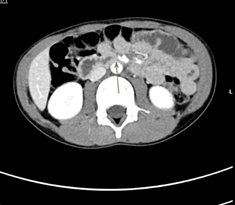

Fig  1: Axial image of IV contrast enhanced CT scan of the abdomen demonstrates gastric dilatation.

The tight and sharp aortomesenteric distance and angle respectively along with the gastric and duodenal dilatation are in favour of superior mesenteric artery syndrome.

Figure 1